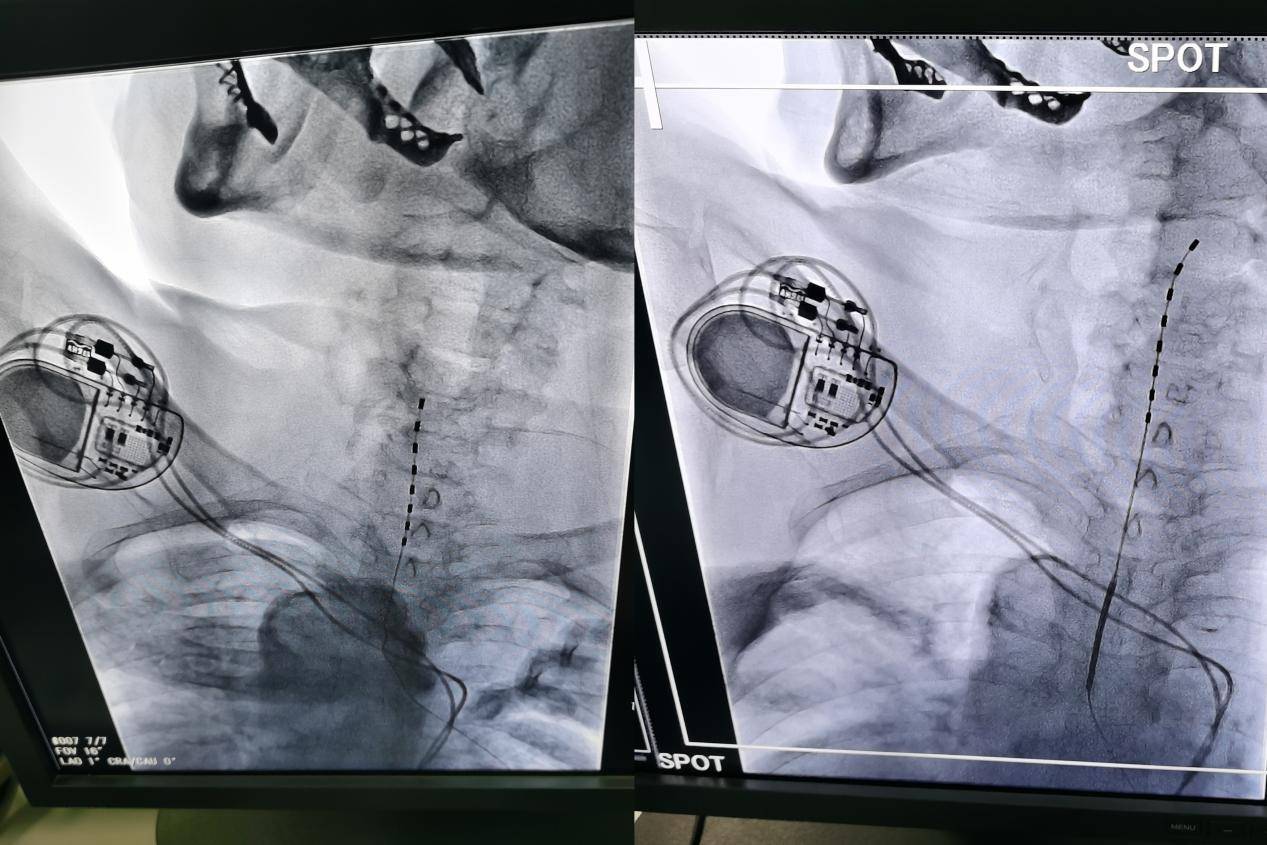

郭主任手术中

郭主任团队为郑阿姨实施了脊髓电刺激镇痛术——这是一种先进的神经调控技术,通过植入脊髓附近的细微电极,释放微弱的电脉冲,阻断疼痛信号向大脑的传递。